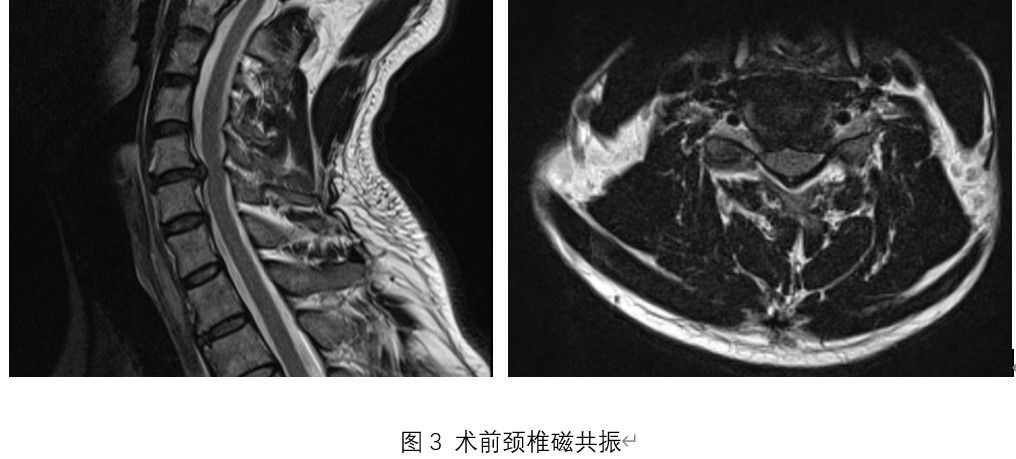

王先生是一名长期受颈椎病困扰的患者,因神经根受压导致上肢麻木、活动受限。入院后王栋主任、李锋涛副主任医师、郭帅主治医师经过详细评估讨论,向王先生推荐了LUSE技术辅助ACDF手术的治疗方案。术中,手术室南强强护士、胡展源护士、麻醉科袁浩峥医生、电生理监护团队孙丽君技师等全程保驾护航。经LUSE技术辅助ACDF手术后,王先生症状显著缓解,术后恢复迅速。